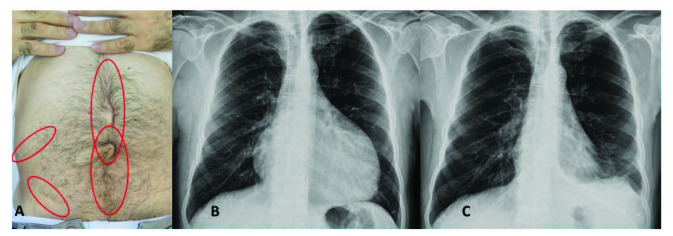

腹膜發(fā)作開(kāi)始局限并迅速蔓延至整個(gè)腹部。腹膜炎癥會(huì)導(dǎo)致典型的腸梗阻癥狀,患者會(huì)遭受?chē)?yán)重的胃痛。體格檢查顯示腹部肌肉僵硬、反跳痛和腸鳴音消失——臨床上這種緊急情況與急腹癥的手術(shù)原因無(wú)法區(qū)分。因此,隱匿性腹部手術(shù)史在良性陣發(fā)性腹膜炎患者中很常見(jiàn)(圖 1A)。在疑似病例中,影像學(xué)檢查可能有助于排除手術(shù)病理。腹部發(fā)作后可能會(huì)出現(xiàn)輕度反彈性腹瀉。盡管有戲劇性的表現(xiàn),但腹膜炎的所有體征和癥狀在 24-72 小時(shí)內(nèi)有效消退,沒(méi)有后遺癥,盡管慢性腹水和腹膜粘連的報(bào)道很少。

圖1:(A) 一位因多次腹部手術(shù)而留下疤痕的患者,(B) 胸部 X 光片顯示大量心包積液,(C) 同一患者用阿那白滯素治療后的胸部 X 光片。

心包炎是一種罕見(jiàn)病癥,見(jiàn)于 1%–2% 的患者。心包炎會(huì)出現(xiàn)胸骨后胸痛和呼吸困難等癥狀。心包填塞可能很少發(fā)生。心電圖顯示 ST 段抬高,胸部 X 光片可能顯示心臟輪廓的短暫擴(kuò)大(圖 1B 和 1C),超聲心動(dòng)圖顯示心包積液。在極少數(shù)情況下,反復(fù)性心包炎可能是良性陣發(fā)性腹膜炎的少有表現(xiàn),這可能與特發(fā)性心包炎相混淆 。